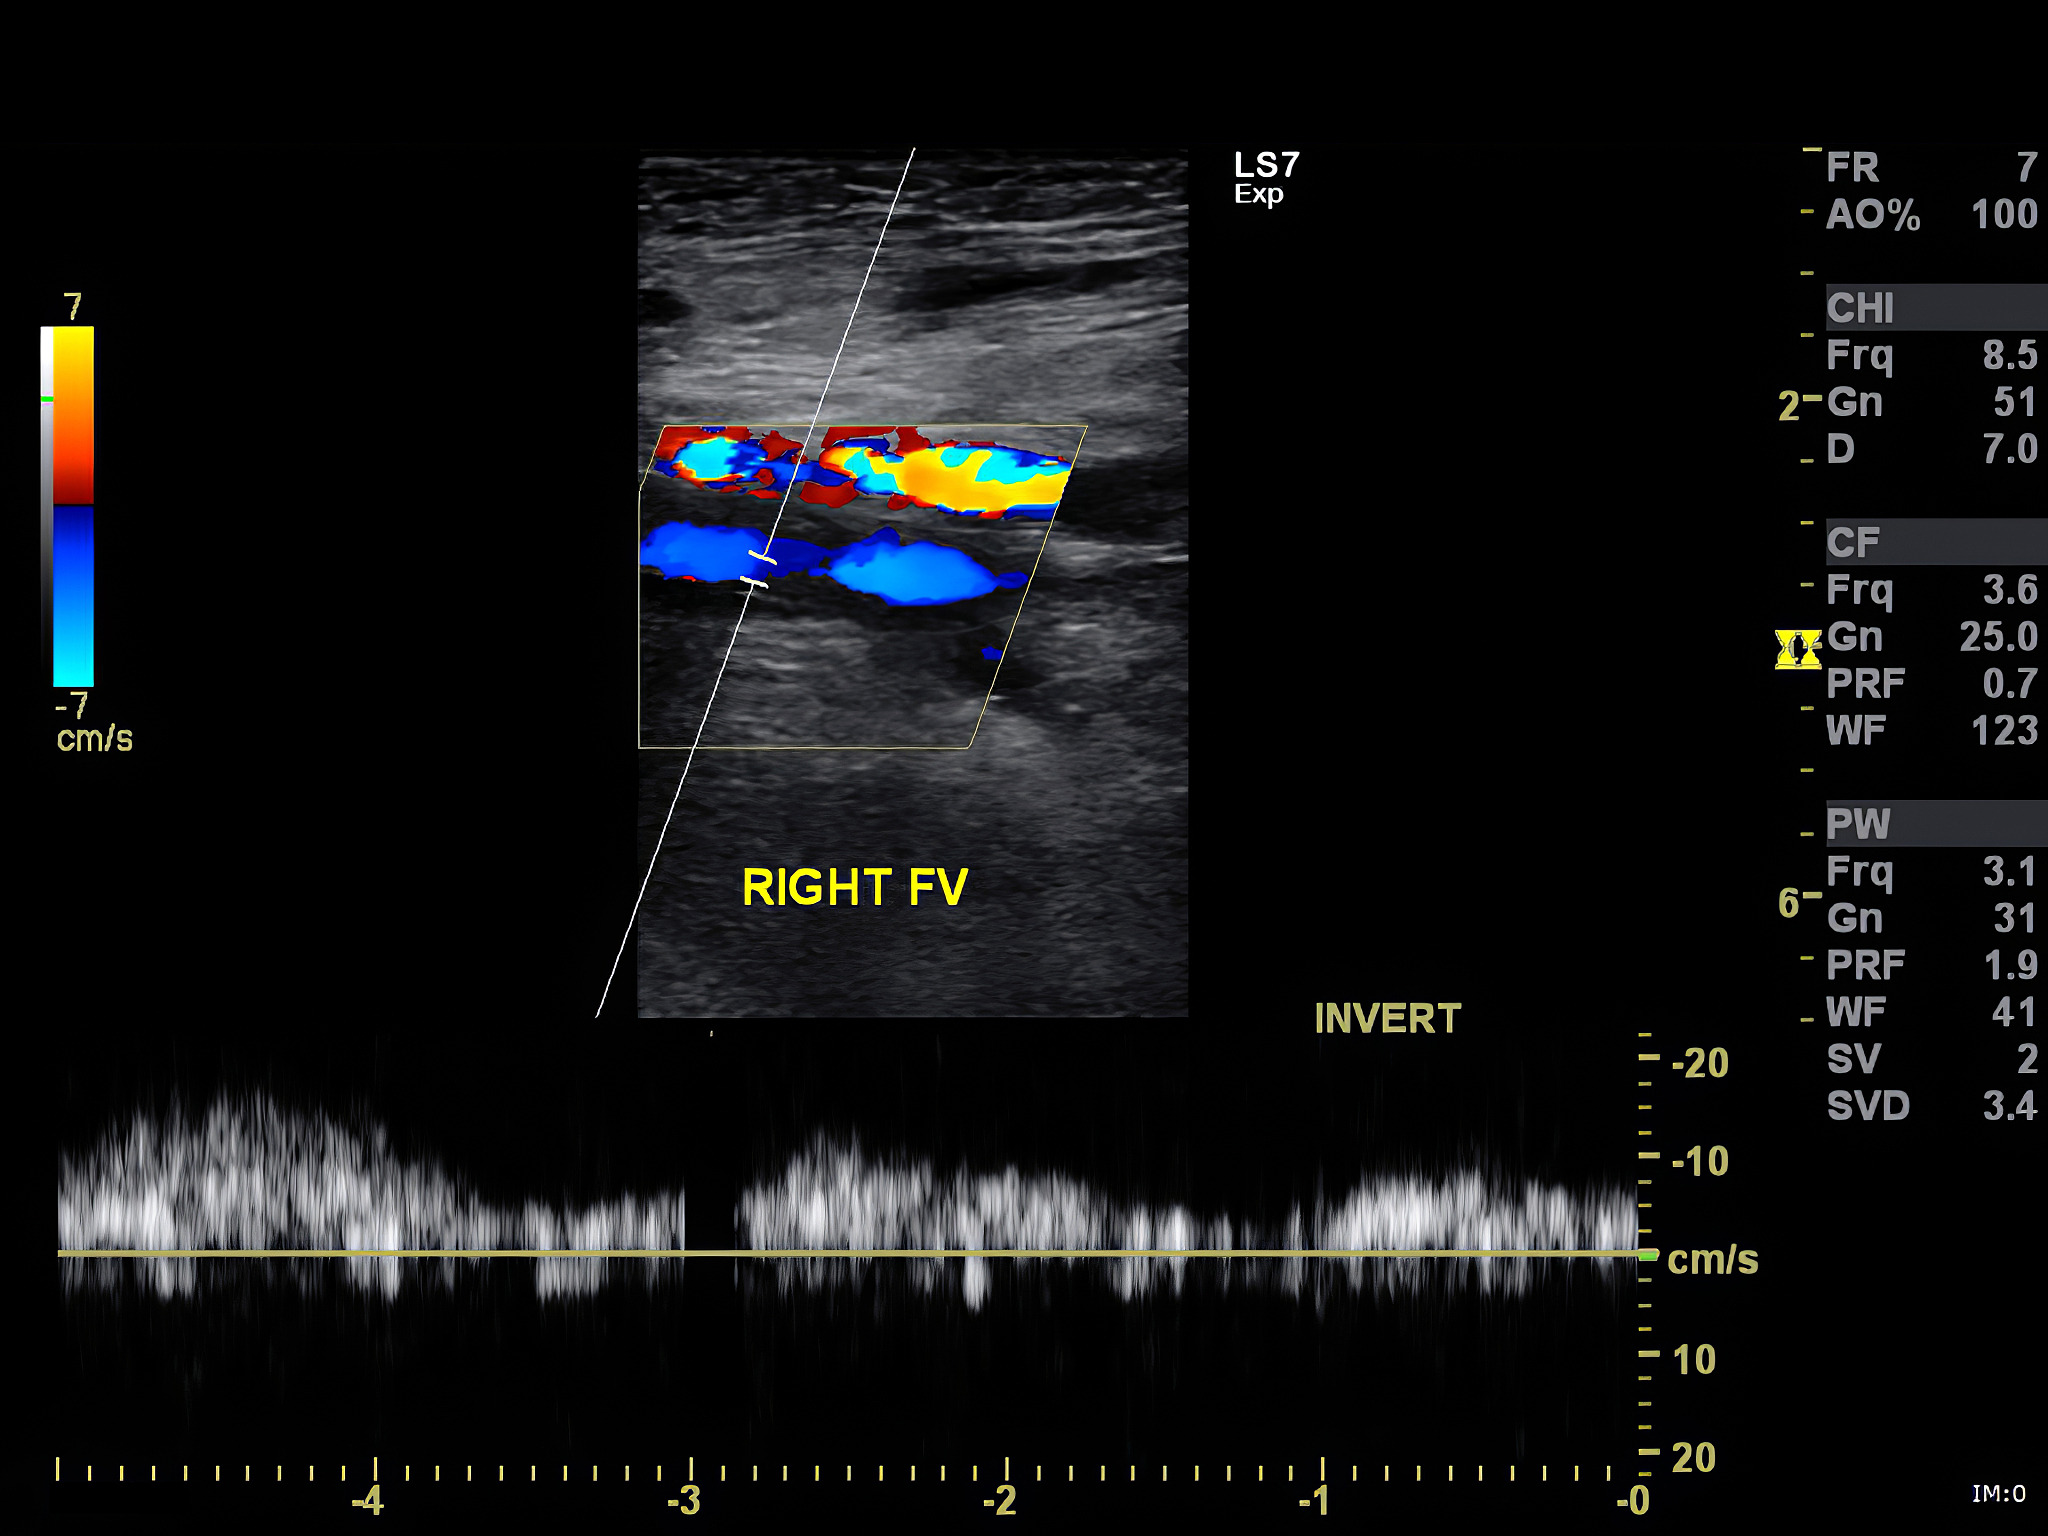

1. 精准诊断,明确病情: 超声引导下精准定位病灶,细针穿刺获取细胞样本,通过细胞学检查可以明确是否存在恶性细胞,为甲状腺癌的诊断提供可靠依据。